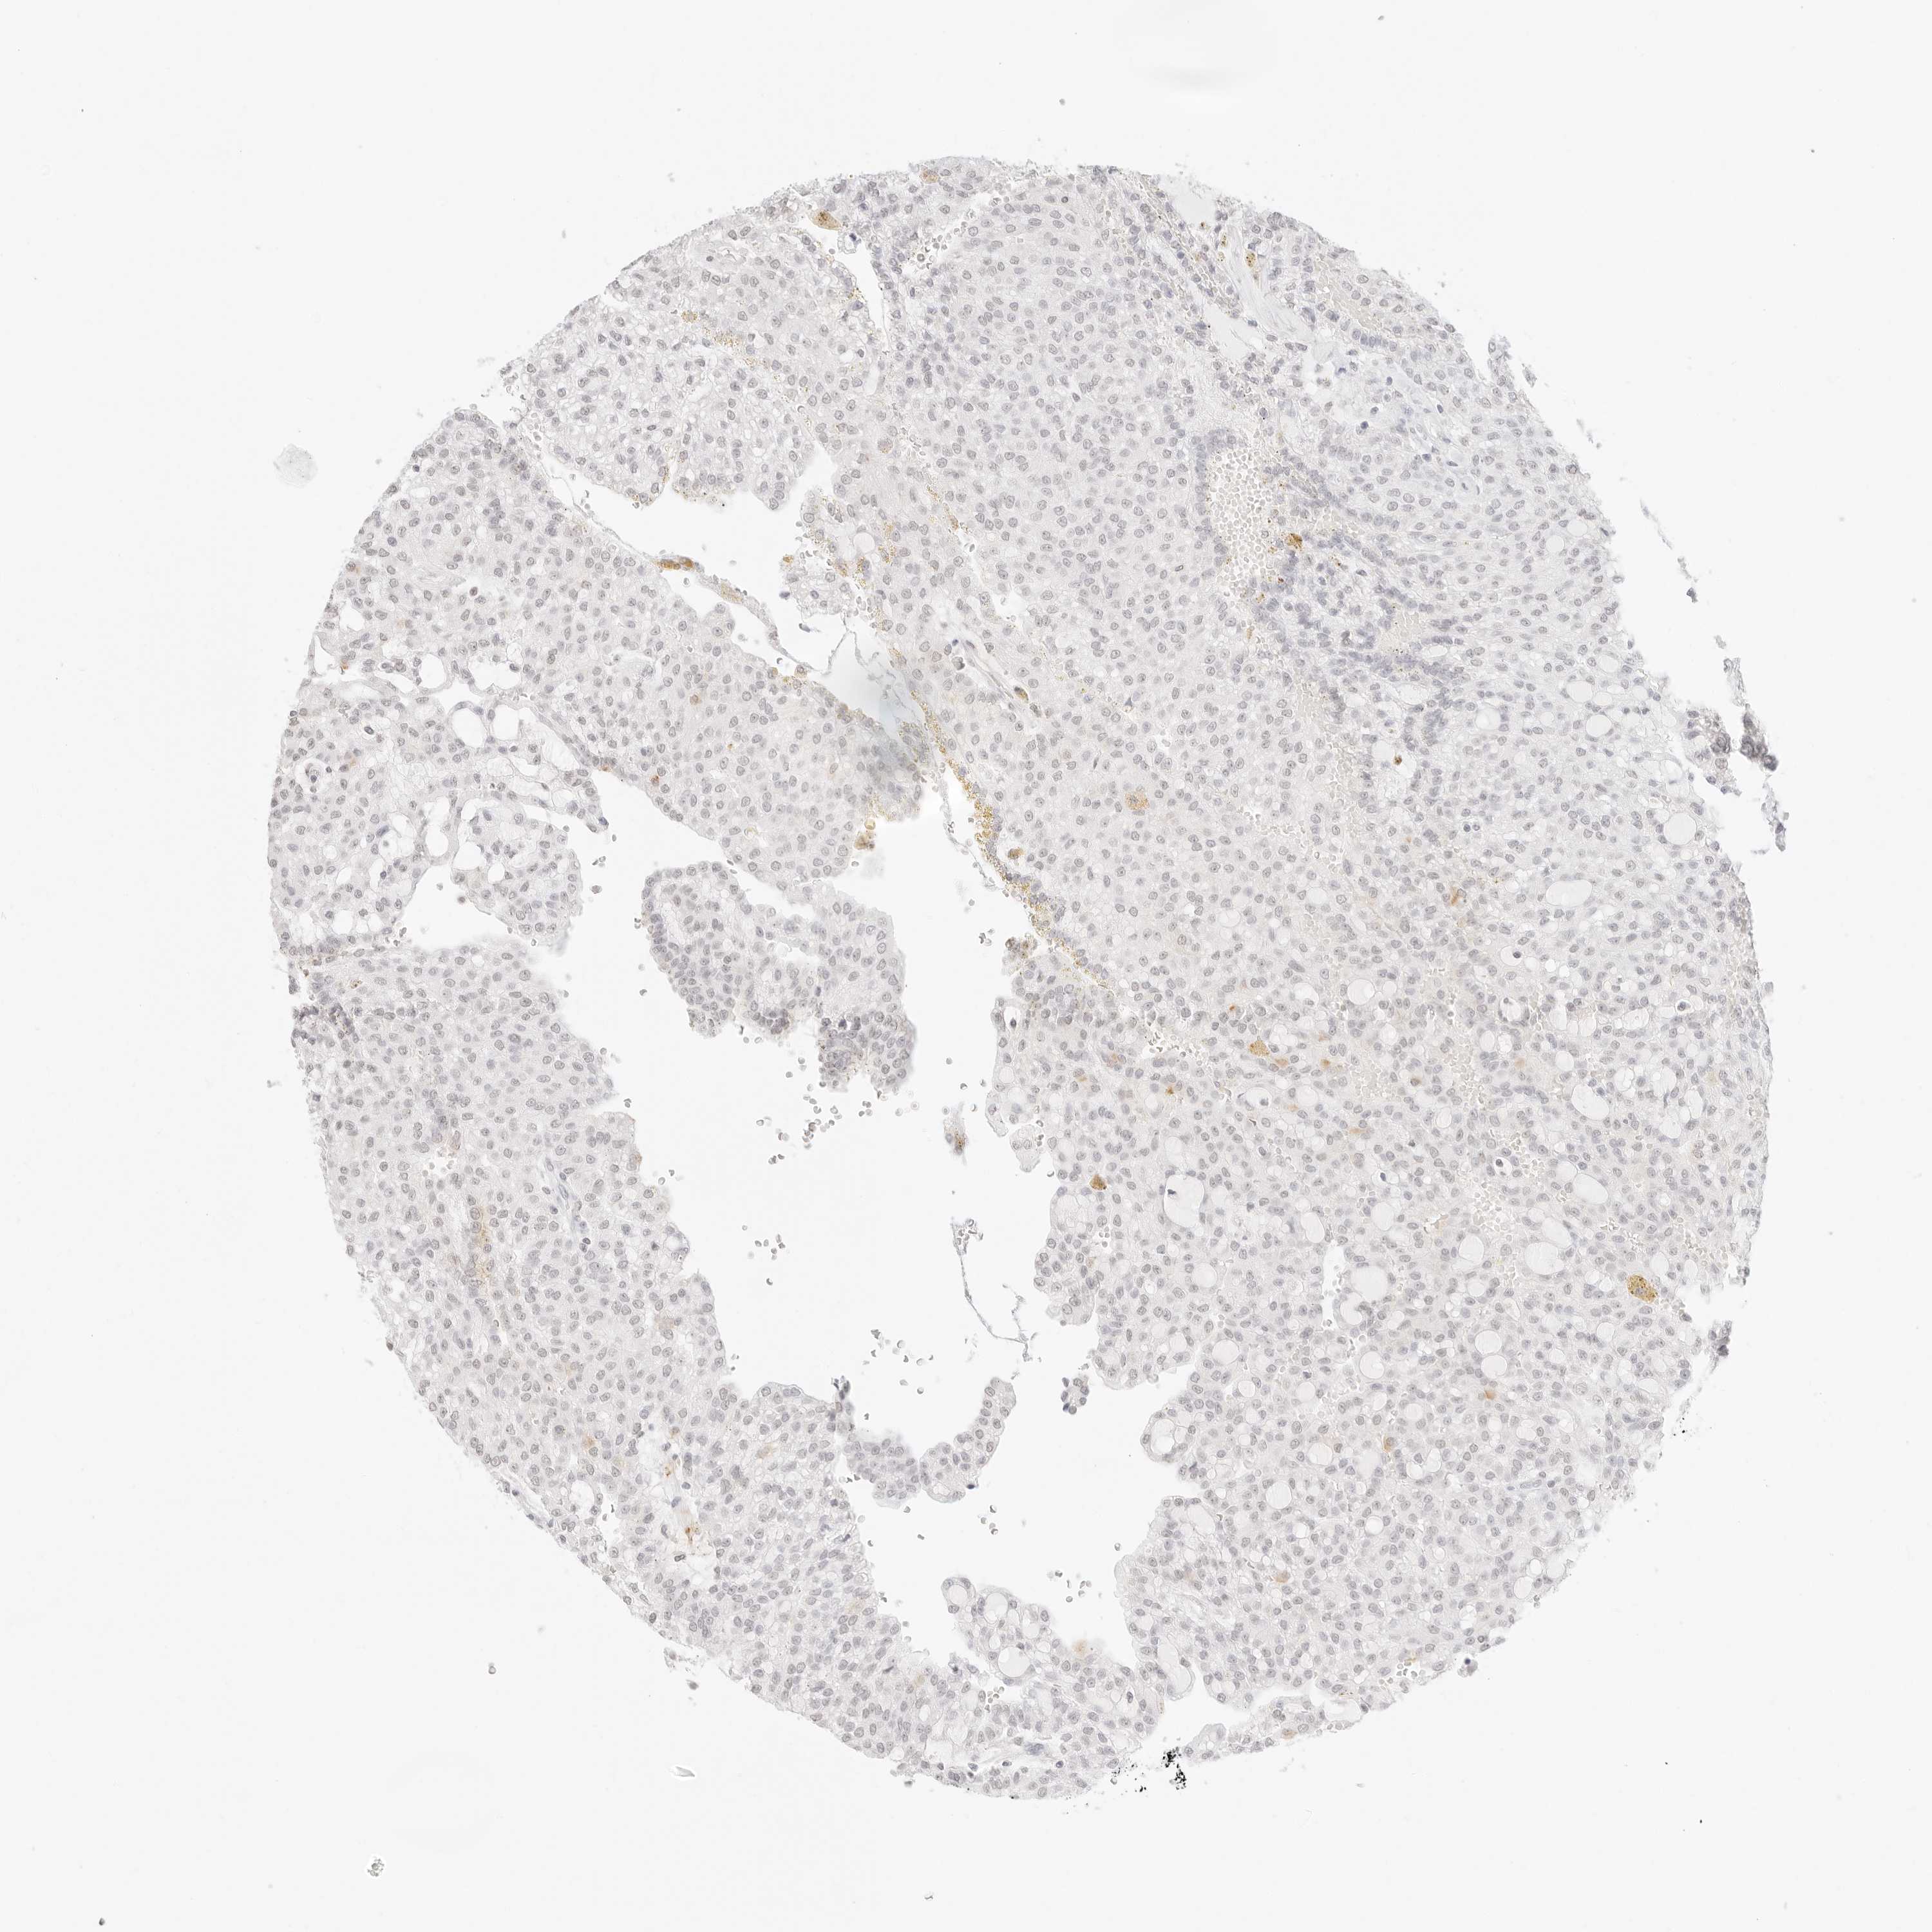

CANCER RENAL CANCER Show tissue menu

KICH TCGA KIRC TCGA KIRC VALIDATION KIRP TCGA PROTEIN RCC CPTAC PROTEIN EXPRESSION

KIDNEY CHROMOPHOBE (TCGA) - Interactive survival scatter ploti

The Survival Scatter plot shows the clinical status (i.e. dead or alive) for all individuals in the patient cohort, based on the same data that underlies the corresponding Kaplan-Meier plots. Patients that are alive at last time for follow-up are shown in blue and patients who have died during the study are shown in red.

The x-axis shows the expression levels (FPKM) of the investigated gene in the tumor tissue at the time of diagnosis. The y-axis shows the follow-up time after diagnosis (years). Both axes are complimented with kernel density curves demonstrating the data density over the axes. The top density plot shows the expression levels (FPKM) distribution among dead (red) and alive patients (blue). The right density plot shows the data density of the survived years of dead patients with high and low expression levels respectively, stratified using the cutoff indicated by the vertical dashed line through the Survival Scatter plot. This cutoff is automatically defined based on the FPKM cutoff that minimizes the p-score. The cutoff can be changed by dragging the vertical line or by entering a cutoff value in the square labeled "Current cut-off".

Under the Survival Scatter plot the p-score landscape (black curve; left axis) is shown together with dead median separation (red curve; right axis). Dead median separation is the difference in median mRNA expression between patients who have died with high and low expression, respectively. It is calculated as follows: median FPKM expression of dead patients with high expression - median FPKM expression of dead patients with low expression. This is intended to aid the user in visually exploring custom cutoffs and the associated p-scores and dead median separation.

Individual patient data is displayed and can be filtered by clicking on one or more of the category buttons on the top of the page. Categories describing expression level and patient information include: high, low, alive, dead, female, male and tumor stages. The scale of the x-axis can be toggled between linear and log-scale by clicking on the "x log" button. Mouse-over function shows TCGA ID, patient information and mRNA expression (FPKM) for each patient.

& Survival analysisi

Kaplan-Meier plots summarize results from analysis of correlation between mRNA expression level and patient survival. Patients were divided based on level of expression into one of the two groups "low" (under cut off) or "high" (over cut off). X-axis shows time for survival (years) and y-axis shows the probability of survival, where 1.0 corresponds to 100 percent.

FBLN5 is not prognostic in Kidney Chromophobe (TCGA)